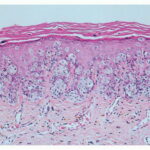

Because not all follicles in a given area are affected, transversely sectioned scalp biopsies may increase the yield of finding the diagnostic histologic features of trichotillomania, including increased numbers of catagen and telogen hairs (most cases) and empty or distorted follicles (greater than 50% of cases) (194). The same study found pigment casts and trichomalacia in less than 50% of cases. When the scalp is also rubbed persistently, epidermal changes of lichen simplex chronicus may be seen in vertical sections. |

Histopathology. In horizontally sectioned biopsies of trichotillomania uncomplicated by the coexistence of other types of alopecia, the density of hair follicles is normal, as is the terminal-to-vellus hair ratio. The diagnostic finding, when seen, is distorted hair follicle anatomy, without inflammation . Specifically, the pulling of hairs can leave behind empty anagen follicles and "torn-away" follicles, the result of plucked hair shafts that retain parts of the hair matrix and root sheaths . Additional microscopic evidence of traumatic injury was published by Royer et al. as the "hamburger sign," describing a vertically oriented split in the hair shaft containing proteinaceous material and erythrocytes, resembling a hamburger within a bun . Damaged follicles enter the resting phase, leading to an increase in the percentage of catagen and telogen hairs, as high as 75% . Often the hairs do not become normal catagen hairs and appear distorted and abnormal . |